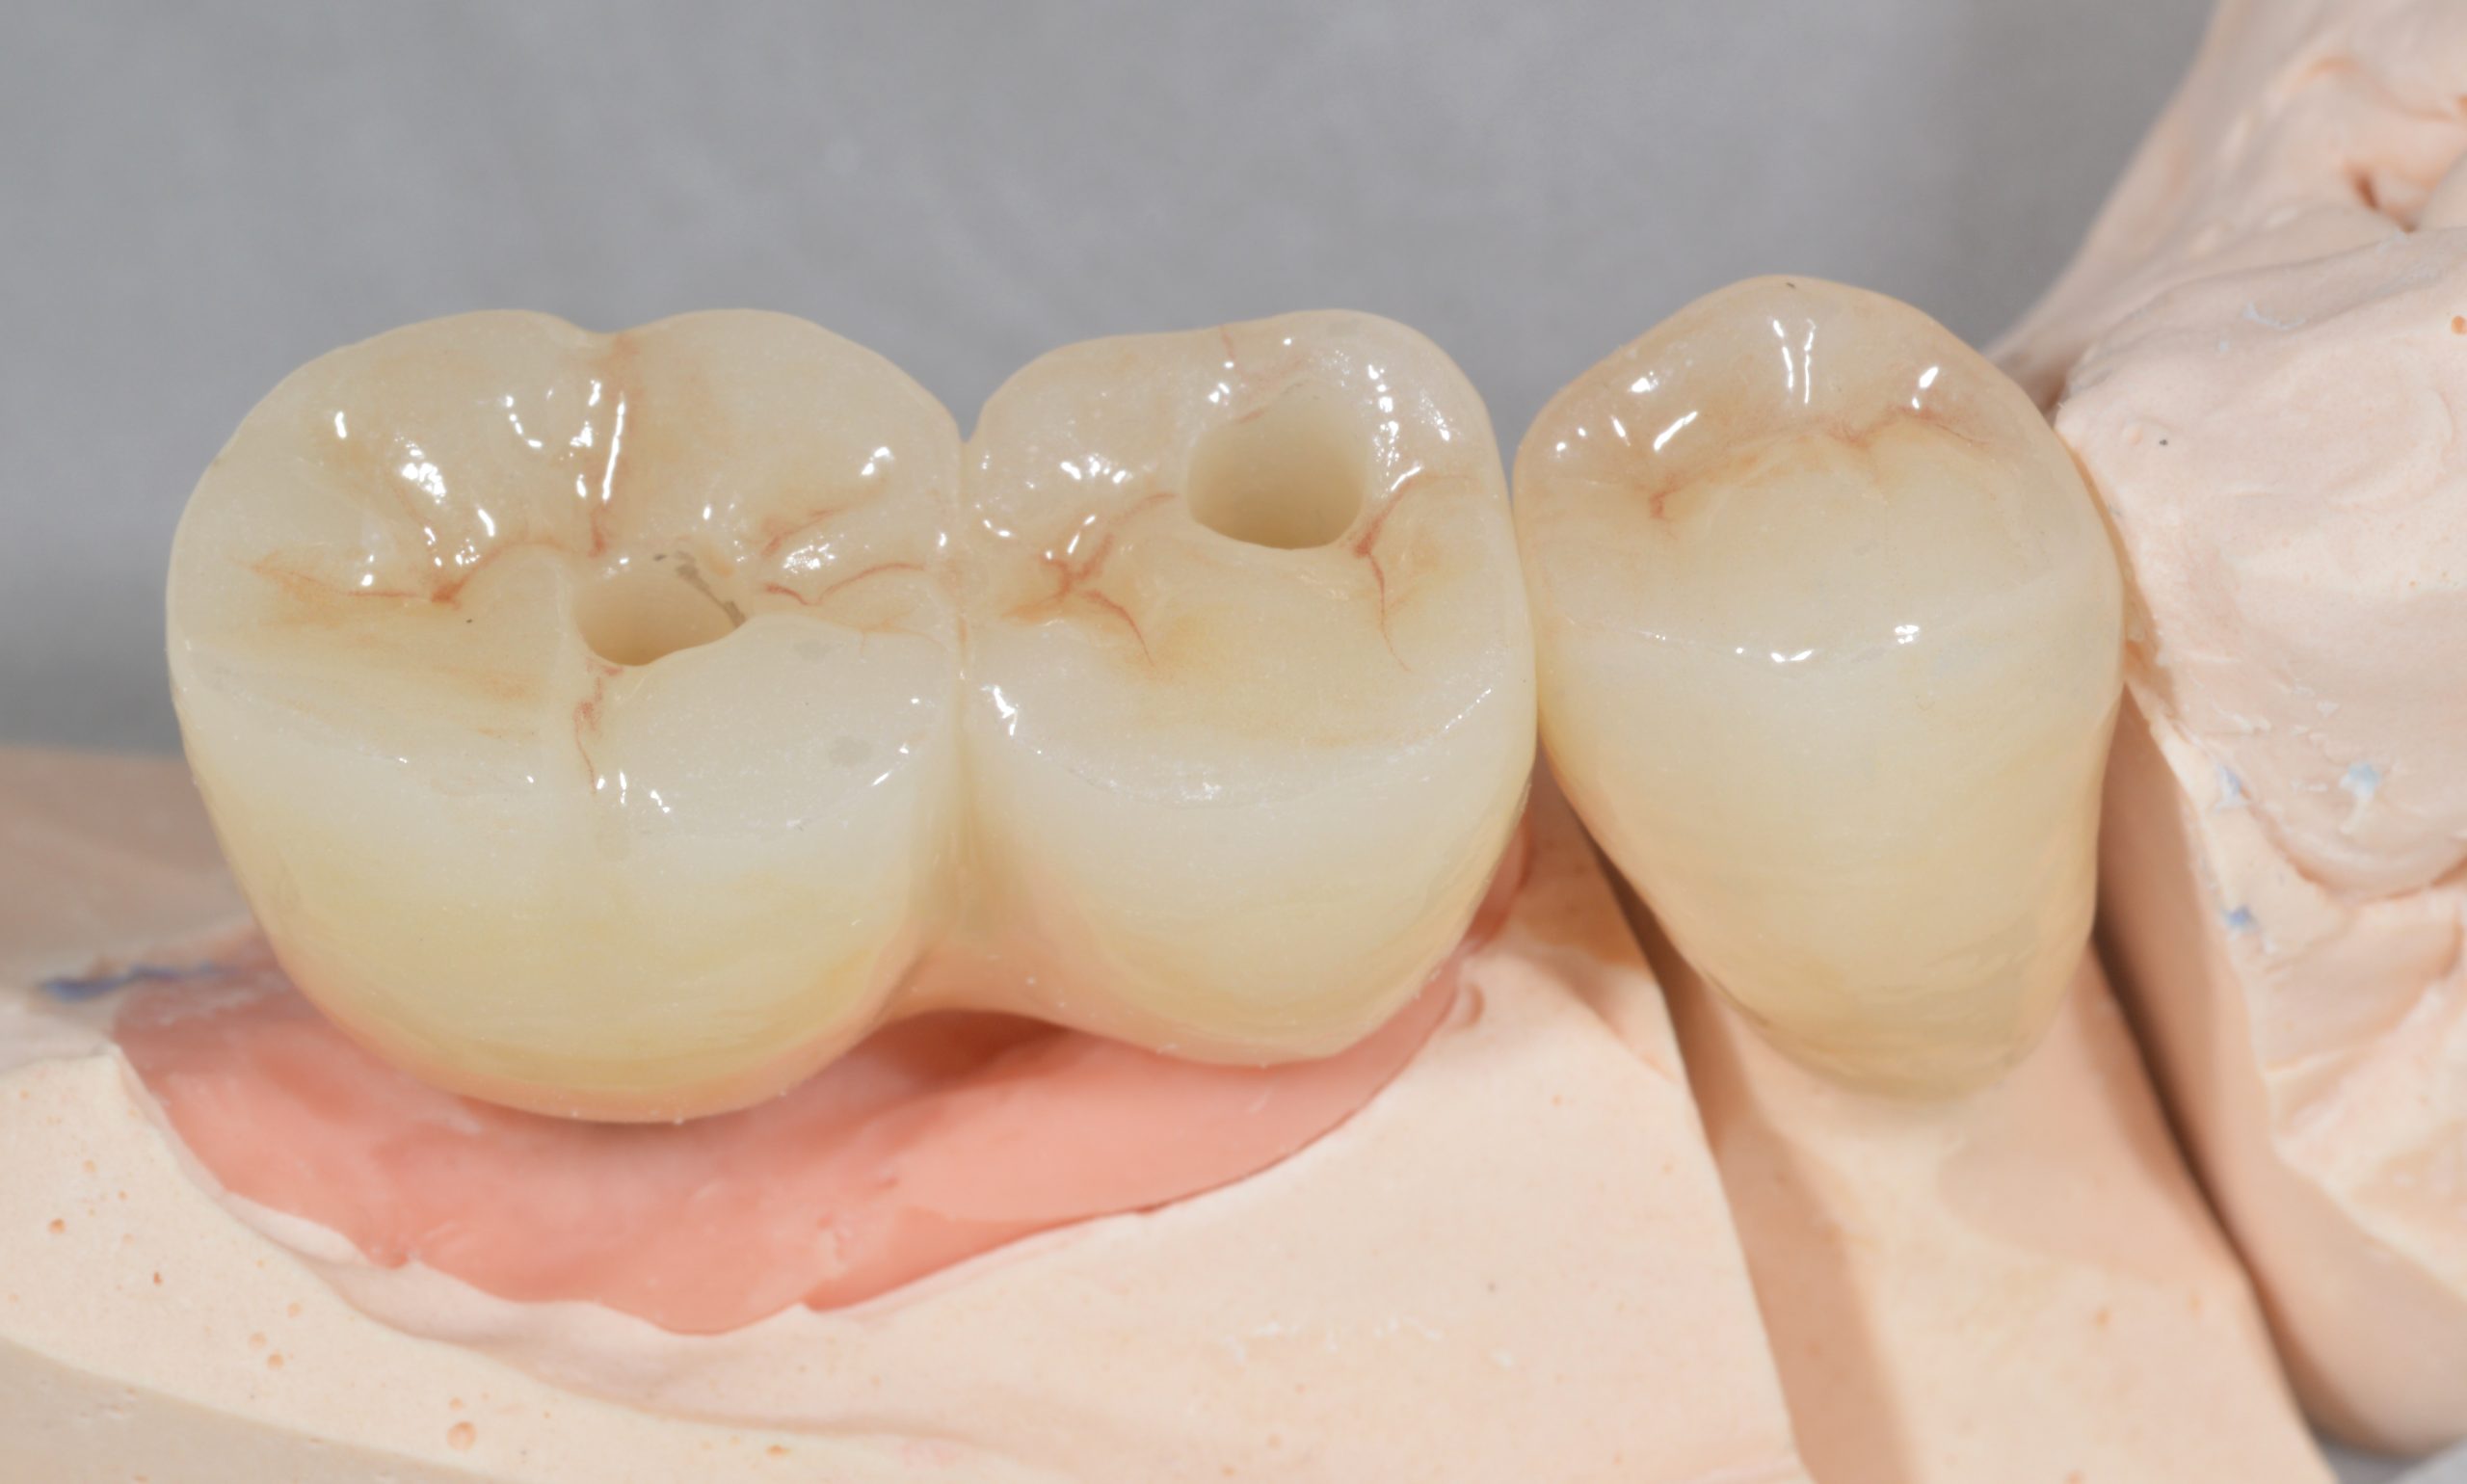

A ZrO2 block with two occlusal access channels was fabricated.

After the two abutments were tightened and filled over the screws, the ZrO2 block was bonded intraorally and the openings were then sealed with plastic material.

In addition, the dental technicians ensured a cleaning-friendly basal passage between 45 and 46. The handling of the interdental brushes was checked and the patient was instructed to attend a regular recall.